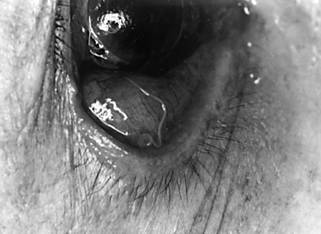

Khi bệnh diễn ra do nhiễm trùng giun chỉ Loa Loa tại mắt thì mi mắt phù nề và ngứa, đôi lúc thấy giun dưới da và có thể sờ thấy được. Kết mạc phù, viêm kết mạc cấp tính, ngứa dữ dội, đôi khi thấy được giun chỉ màu vàng nhạt, mảnh, chiều dài từ 3-6 cm rất dễ di động.

Hình 6